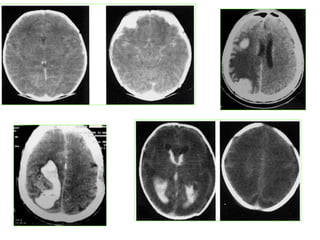

A.V.C HEMORRAGIQUE :

TDM: de première intention, en urgence , SPC

ANGIOSCANNER: dg+, topographique et stratégie thérapeutique

HEMORRAGIE INTRA CEREBRALE :

– TDM(SPC)+++:

– STADE AIGU: HEMATOME spontanément hyperdense /

– Œdème péri lésionnel hypodense/effet de masse maximal

– STADE SUB AIGU: diminution de l’hyperdensité de

l’hématome de la périphérie vers le centre → isodense →

hypodense = réduction de taille

del’hématome/œdème/effet de masse

– STADE CHRONIQUE: cavité porencéphalique sans

rehaussement avec dilatation des sillons corticaux et

ventriculaire en regard

• AVC hémorragique